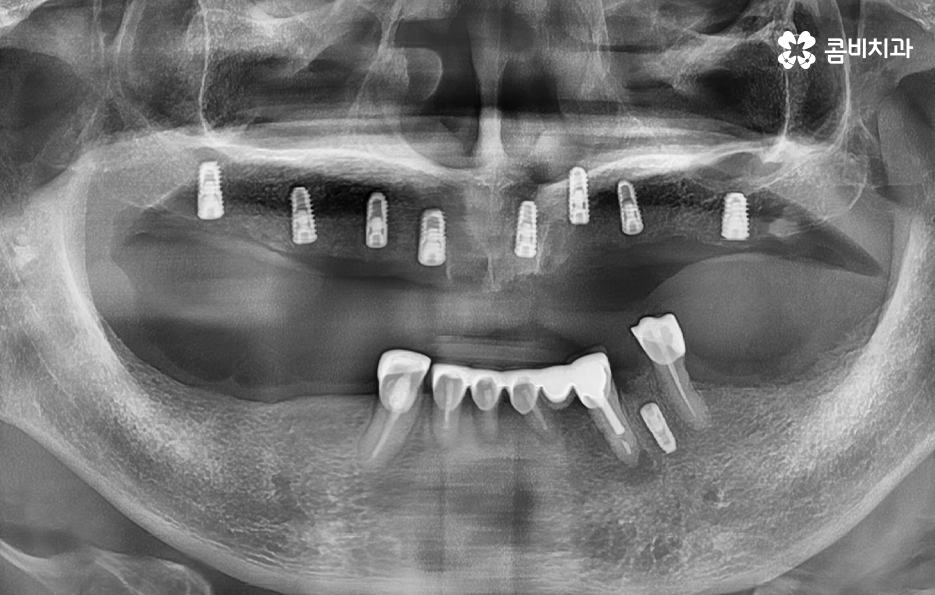

특히 만65세 이상 건강보험 임플란트 혜택을 적용받을 수 있는 환자분들이라면 건강보험을 통해 임플란트 비용에 대해 본인부담률 30%로 비용 부담을 줄일 수 있다는 이점도 있지만 앞서 말씀드린 통계에서도 알 수 있듯이 60대 이후에는 임플란트 치료 계획에 있어서 섬세한 치료 계획이 중요하기 때문에 비용을 줄이는 것도 중요하겠지만 건강하고 안전한 치료와 향후 수명 관리를 고려하여 치과 선택이 중요하다고 할 수 있어요

정리하면 임플란트 나이 단순히 나이만으로 치료 계획에 대해 쉽게 판단하기는 어렵겠지만 통계적으로 볼 때 치아의 주된 상실 원인과 임플란트의 원리에서 잇몸 뼈의 중요성을 따져볼 때는 젊은 환자분들에 비해 60대 이후 환자분들이라면 뼈이식을 추가로 받아야 한다거나 회복력과 전신질환에 대해서도 충분히 좀더 감안하여 치료 계획을 디테일하게 세울 필요가 있다는 것을 알 수 있는데요

따라서 다 같은 임플란트 치료로 생각하기 보다는 특히 고령의 환자분 일수록 노인 임플란트에 대한 경험과 실력을 갖춘 치과의사와 함께 하는 것이 중요하며 오래 믿고 유지관리 받을 수 있는 치과인지 잘 따져보시고 판단하실 필요가 있어요